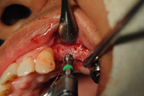

施行鼻竇升高術及骨粉充填。

X光片可見兩植體在鼻竇下緣。